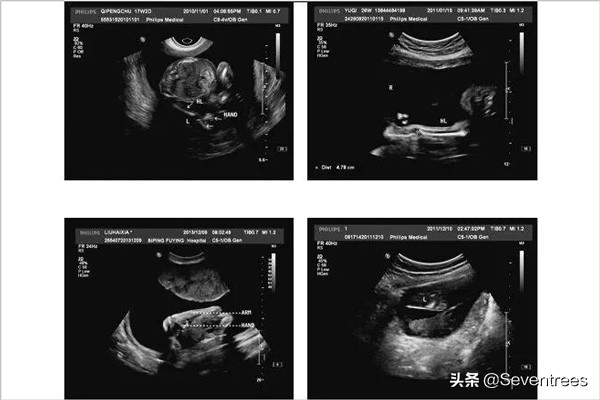

因此,产检尤为重要。一方面,产检可以指导孕妇行为,教她们怎样孕育更健康的宝宝,另一方面,也可以发现怀孕中的各种问题,并及时治疗或处理。其中涉及胎儿的,如果发现严重畸形,很多都只能提前终止。ntb超、唐氏筛查、无创dna筛查、有创染色体检查、排畸b超等都是目前来说十分有效的产前诊断手段,ntb超、唐氏筛查和排畸b超之间不能相互替代。